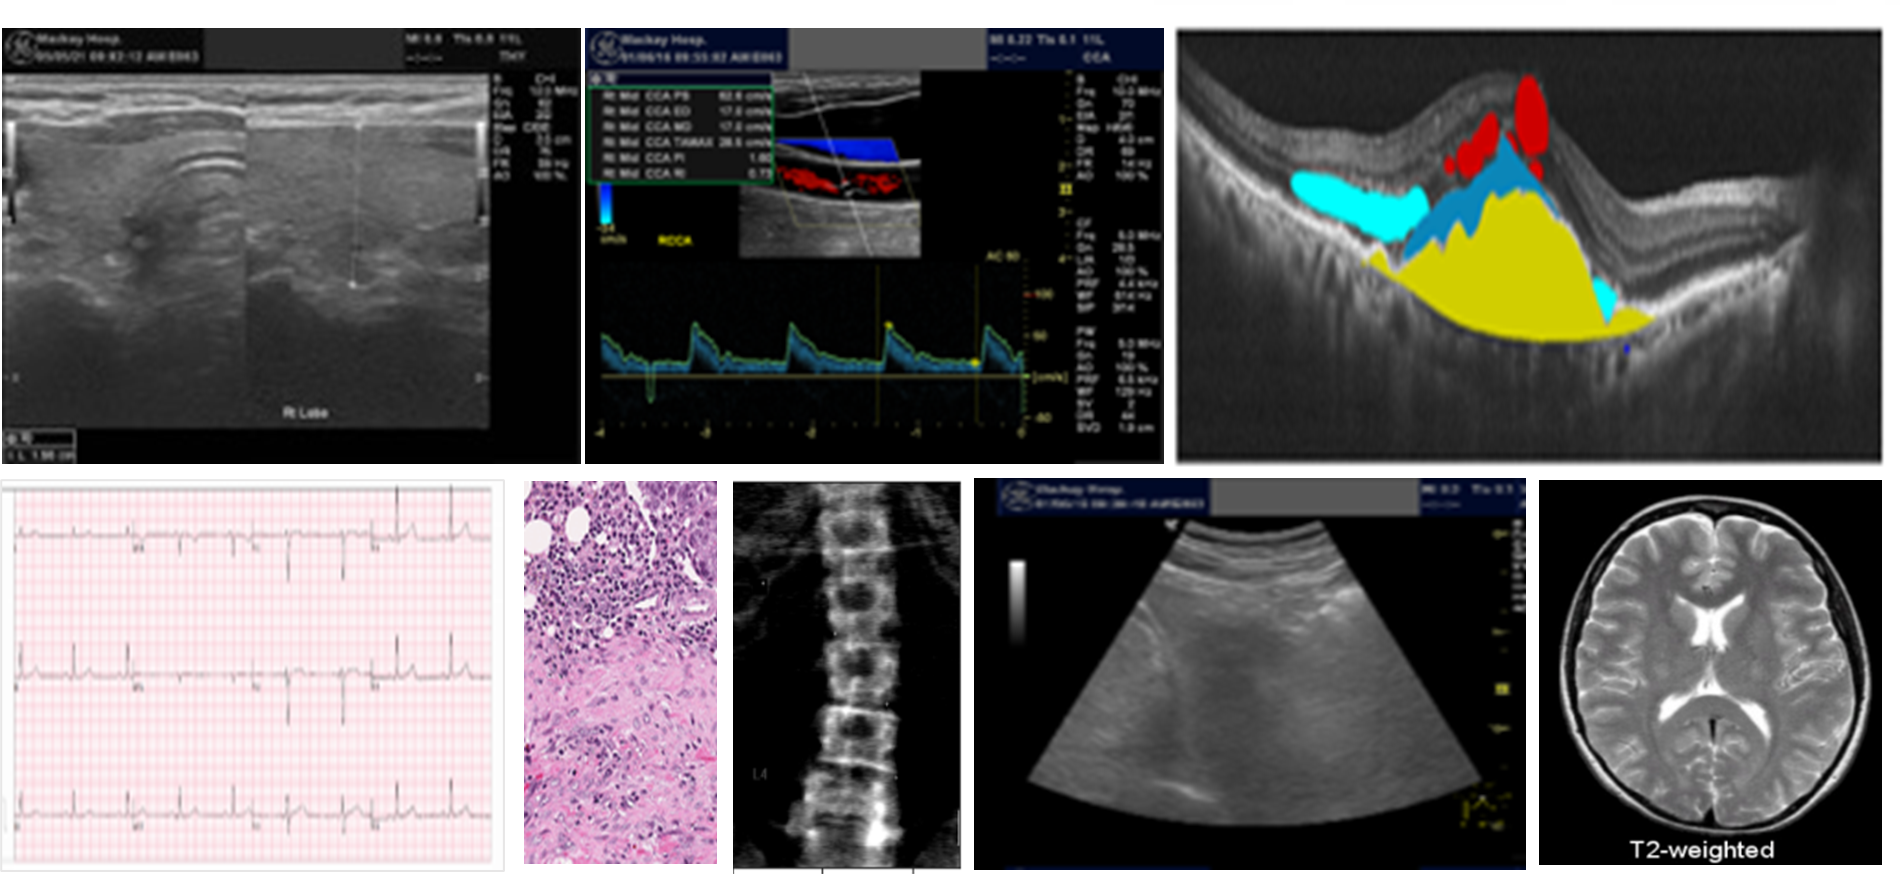

(B) Integration Research and Product Implementation of Smart Health and Precision Health

Objective: By combining medical imaging, electronic health records, and multi-OMICS data, we strive to develop automated tools for sample segmentation, lesion annotation, disease diagnosis, and risk assessment systems. We aim to improve disease classification, prevention, and treatment response across various medical conditions by employing deep learning, machine learning, and statistical learning techniques.